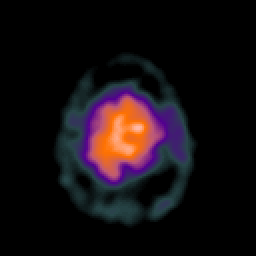

SPECT TC Study #2 -- Slice #46

[Home][Help][Clinical][Tour 1][Tour 2][Tour 3] Slice 46